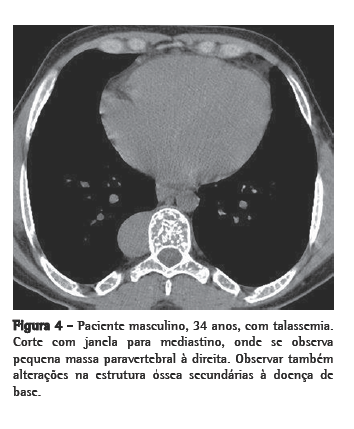

Dos seis pacientes, quatro apresentaram massas paravertebrais inferiores. Em três, elas eram bilaterais e relativamente simétricas, e em um era unilateral, à direita. Quanto ao conteúdo das massas, em três pacientes havia presença de tecido adiposo, sendo que em um desses o material gorduroso era bastante significativo. Em um paciente, as massas eram homogêneas, com densidade de partes moles (Figuras 1a e b, 2a e b).

Radiograficamente, a HEM intratorácica geralmente se apresenta sob a forma de múltiplas massas paravertebrais, com densidade de partes moles, na maioria das vezes bilaterais, lobuladas, com limites bem definidos e sem calcificações ou erosões ósseas associadas.(1,4,5,9) Isso é importante para o diagnóstico diferencial de neurofibromas paravertebrais, que em geral têm alterações ósseas associadas.(4,10) Contudo, evidências de lesões ósseas relacionadas à doença de base são achados comuns. Essas massas geralmente determinam, nas radiografias do tórax, um aspecto de duplo contorno cardíaco, lobulado, na incidência em frontal, assim como um aspecto de massa lobulada projetada sobre os corpos vertebrais inferiores na incidência em perfil.(13)

Através da TC, podem ser observadas massas com densidade de partes moles, em sua maioria homogêneas, com características semelhantes às descritas na radiologia convencional,(1,2,5,6) que podem ou não ser realçadas após a administração do meio de contraste.(4,10) Este método de imagem é importante para analisar a estrutura interna das lesões, particularmente quando ricas em gordura,(5) para avaliar a presença de outras massas paracostais e para detectar alterações ósseas associadas a certas doenças hematológicas, como a talassemia e a anemia falciforme.(6) Nos casos relacionados a talassemia, anemia falciforme ou metaplasia mielóide, pode ocorrer um alargamento das cavidades medulares das costelas.(5)